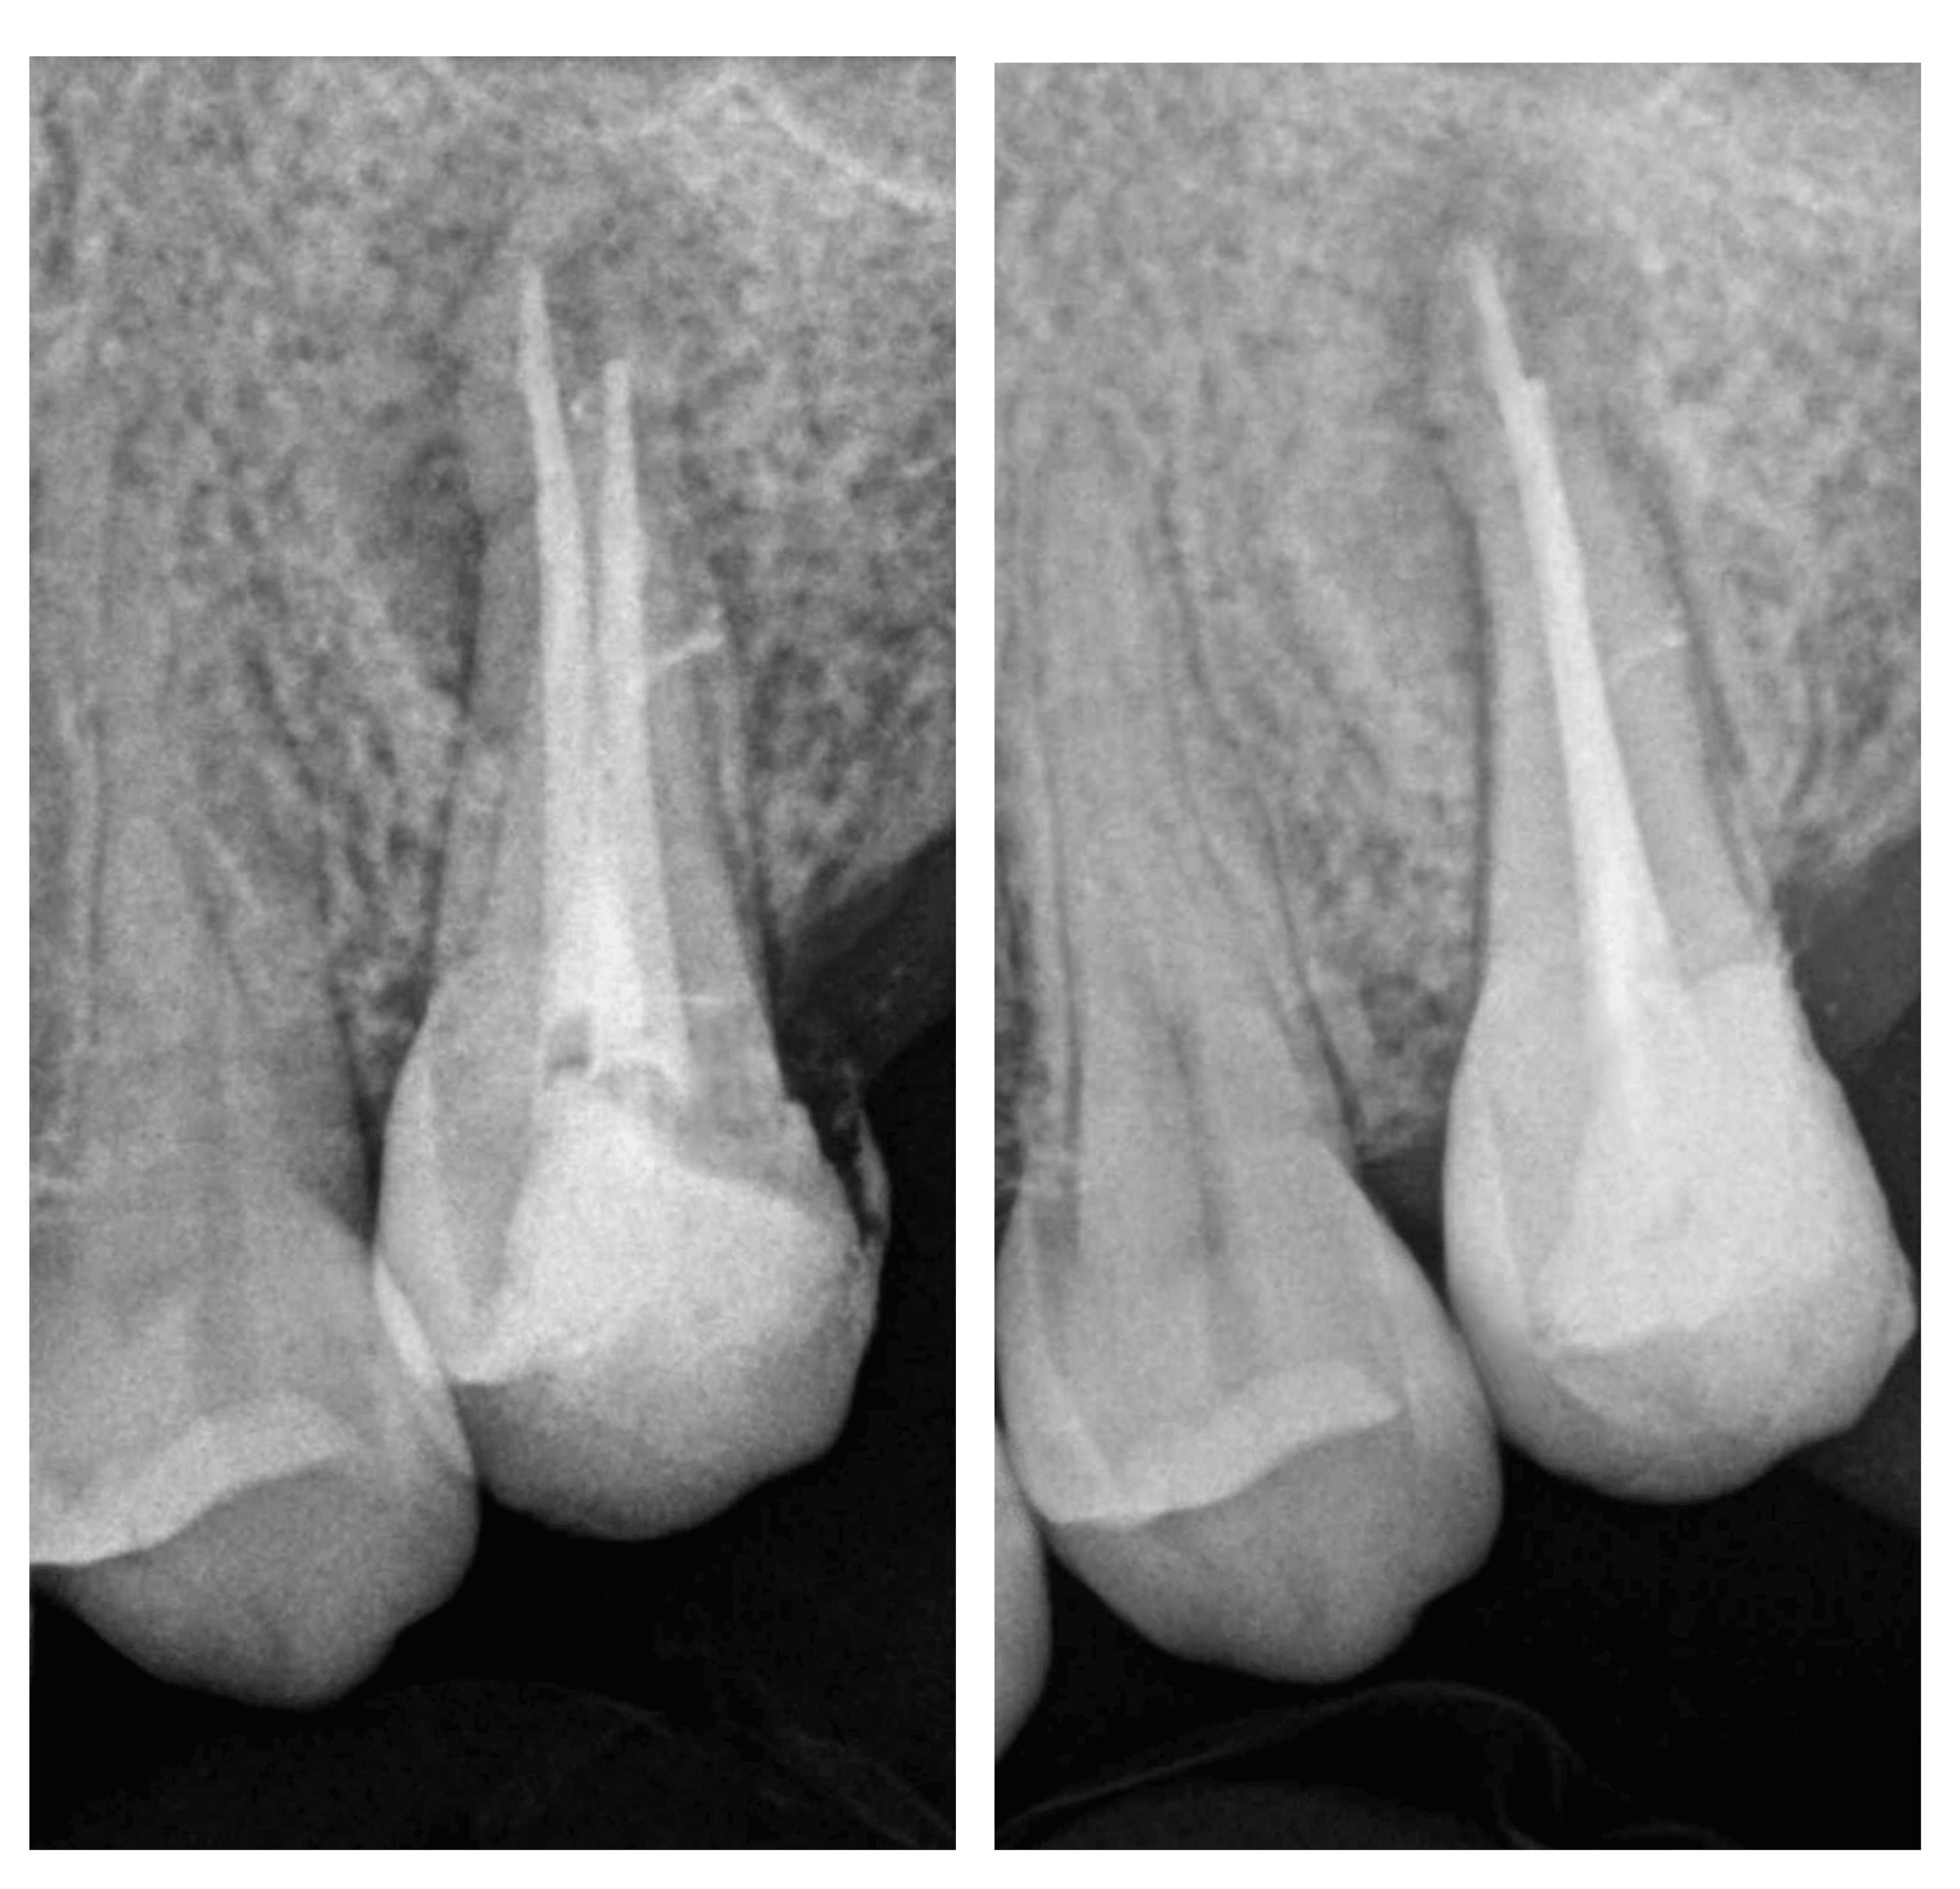

Figure 1 from Interappointment Flareup in Endodontics A Case Report Endodontic Flare-Up Pdf Rakesh mittal abstract numerous hypothetical mechanisms responsible for pain. Review article an overview dr. Pdf | endodontic treatment corresponds to a combined chemical and mechanical approach, followed by a three dimensional hermetic obturation, that. “periapical lesion” and “preoperative pain” were found as the most important risk factors that showed the strongest impacts on. Endodontic Flare-Up Pdf.